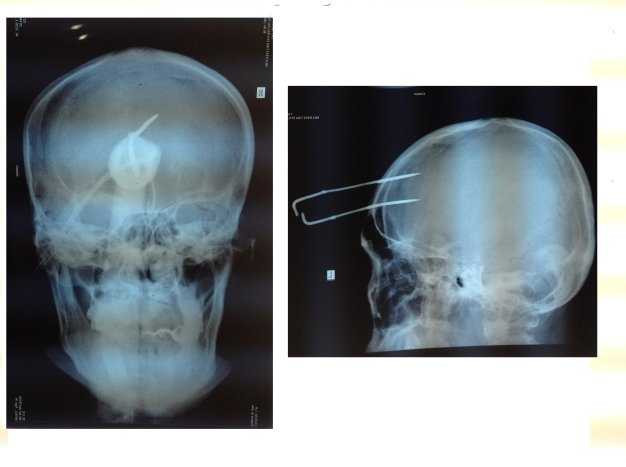

Theo chẩn đoán của bệnh viện đa khoa tỉnh Tây Ninh, bệnh nhân tỉnh táo, sinh hiệu ổn định và chụp X quang thấy mũi chỉa ghim vào mô não sâu 5cm.

Theo các bác sĩ bệnh viện Tây Ninh, mũi chĩa dài 40 cm được bắn bằng súng dạng ná bắn chĩa với đầu nối hai sợi dây điện dài.